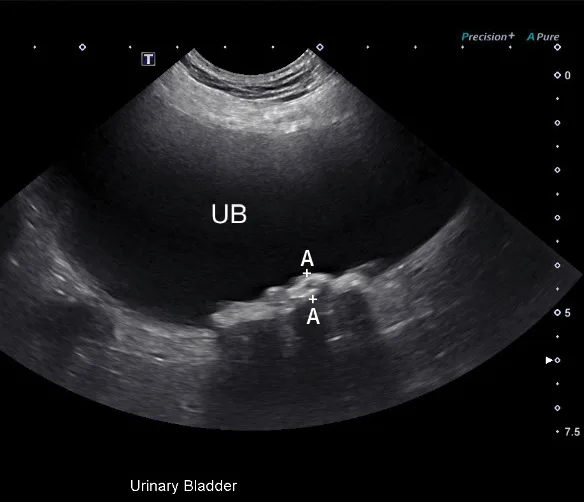

2. Identification of Peritoneal, Pleural, & Pericardial Effusion

Patients with cavitary effusion can have a range of clinical signs, many of which are nonspecific because cavitary effusions are sequelae to a variety of disease processes.5 Ultrasonography is useful in the identification and sampling of effusion fluid in cats and dogs and is more sensitive in the detection of smaller volumes than radiography.6 Primary body cavities to evaluate for effusion include the abdomen (peritoneal space), thorax (pleural space), and pericardial space (Figure 2).5

FIGURE 2

Abdominal effusion (A; asterisk) adjacent to a normal spleen (arrow). Abdominal carcinomatosis with secondary neoplastic effusion was diagnosed. Left parasternal short-axis view of a heart with pericardial (B; asterisks) and pleural effusion (arrow).

The abdomen is most commonly evaluated with the patient in dorsal or lateral recumbency, but scanning the dependent portion with the patient in lateral recumbency can be helpful if only a small amount of effusion is present (see Suggested Reading).6,7 Evaluation for pleural effusion is performed with the patient standing or in ventral recumbency and should begin at the eighth to ninth intercostal space at the level of the costochondral junction. This space is also recommended when thoracocentesis is used in these patients.8 Evaluation for pericardial effusion in the right third to fifth intercostal space at the level of the costochondral junction provides the best acoustic window to the heart.5

Cavitary effusion is normally anechoic on ultrasound but can differ based on fluid type.6 Echogenicity and cytologic classification of effusion is based on cellular and protein content, increasing in echogenicity from pure transudate (anechoic) to modified transudate (variably echoic) and exudate (hyperechoic)6,9; however, the echogenicity of cavitary fluid can vary; thus, fluid analysis is required to confirm the exact nature of the fluid.